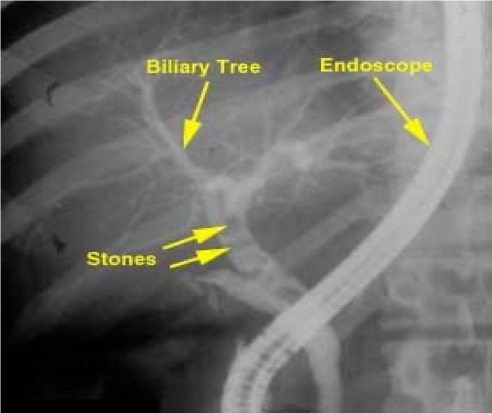

c) Endoscopic retrograde cholangiopancreatography (ERCP): ERCP is an invasive diagnostic and therapeutic investigation which outline the biliary and pancreatic system by injecting contrast through a cannula inserted into the papilla of Vater by means of side viewing endoscope passed into the duodenum. it gives more detailed information than ultrasound and allows endoscopic extraction of common bile duct stones, biopsy of periampullary tumors, and relief of obstructive jaundice by stent insertion. complications of ERCP included acute pancreatitis, cholangitis, duodenal perforation and bleeding. *NEVER USED IN CASE OF CANCER - COMPLICATED CHOLANGITIS *

ERCP showing stone in the bile ducts

ERCP - CBD Stone

- Sign of filling defect